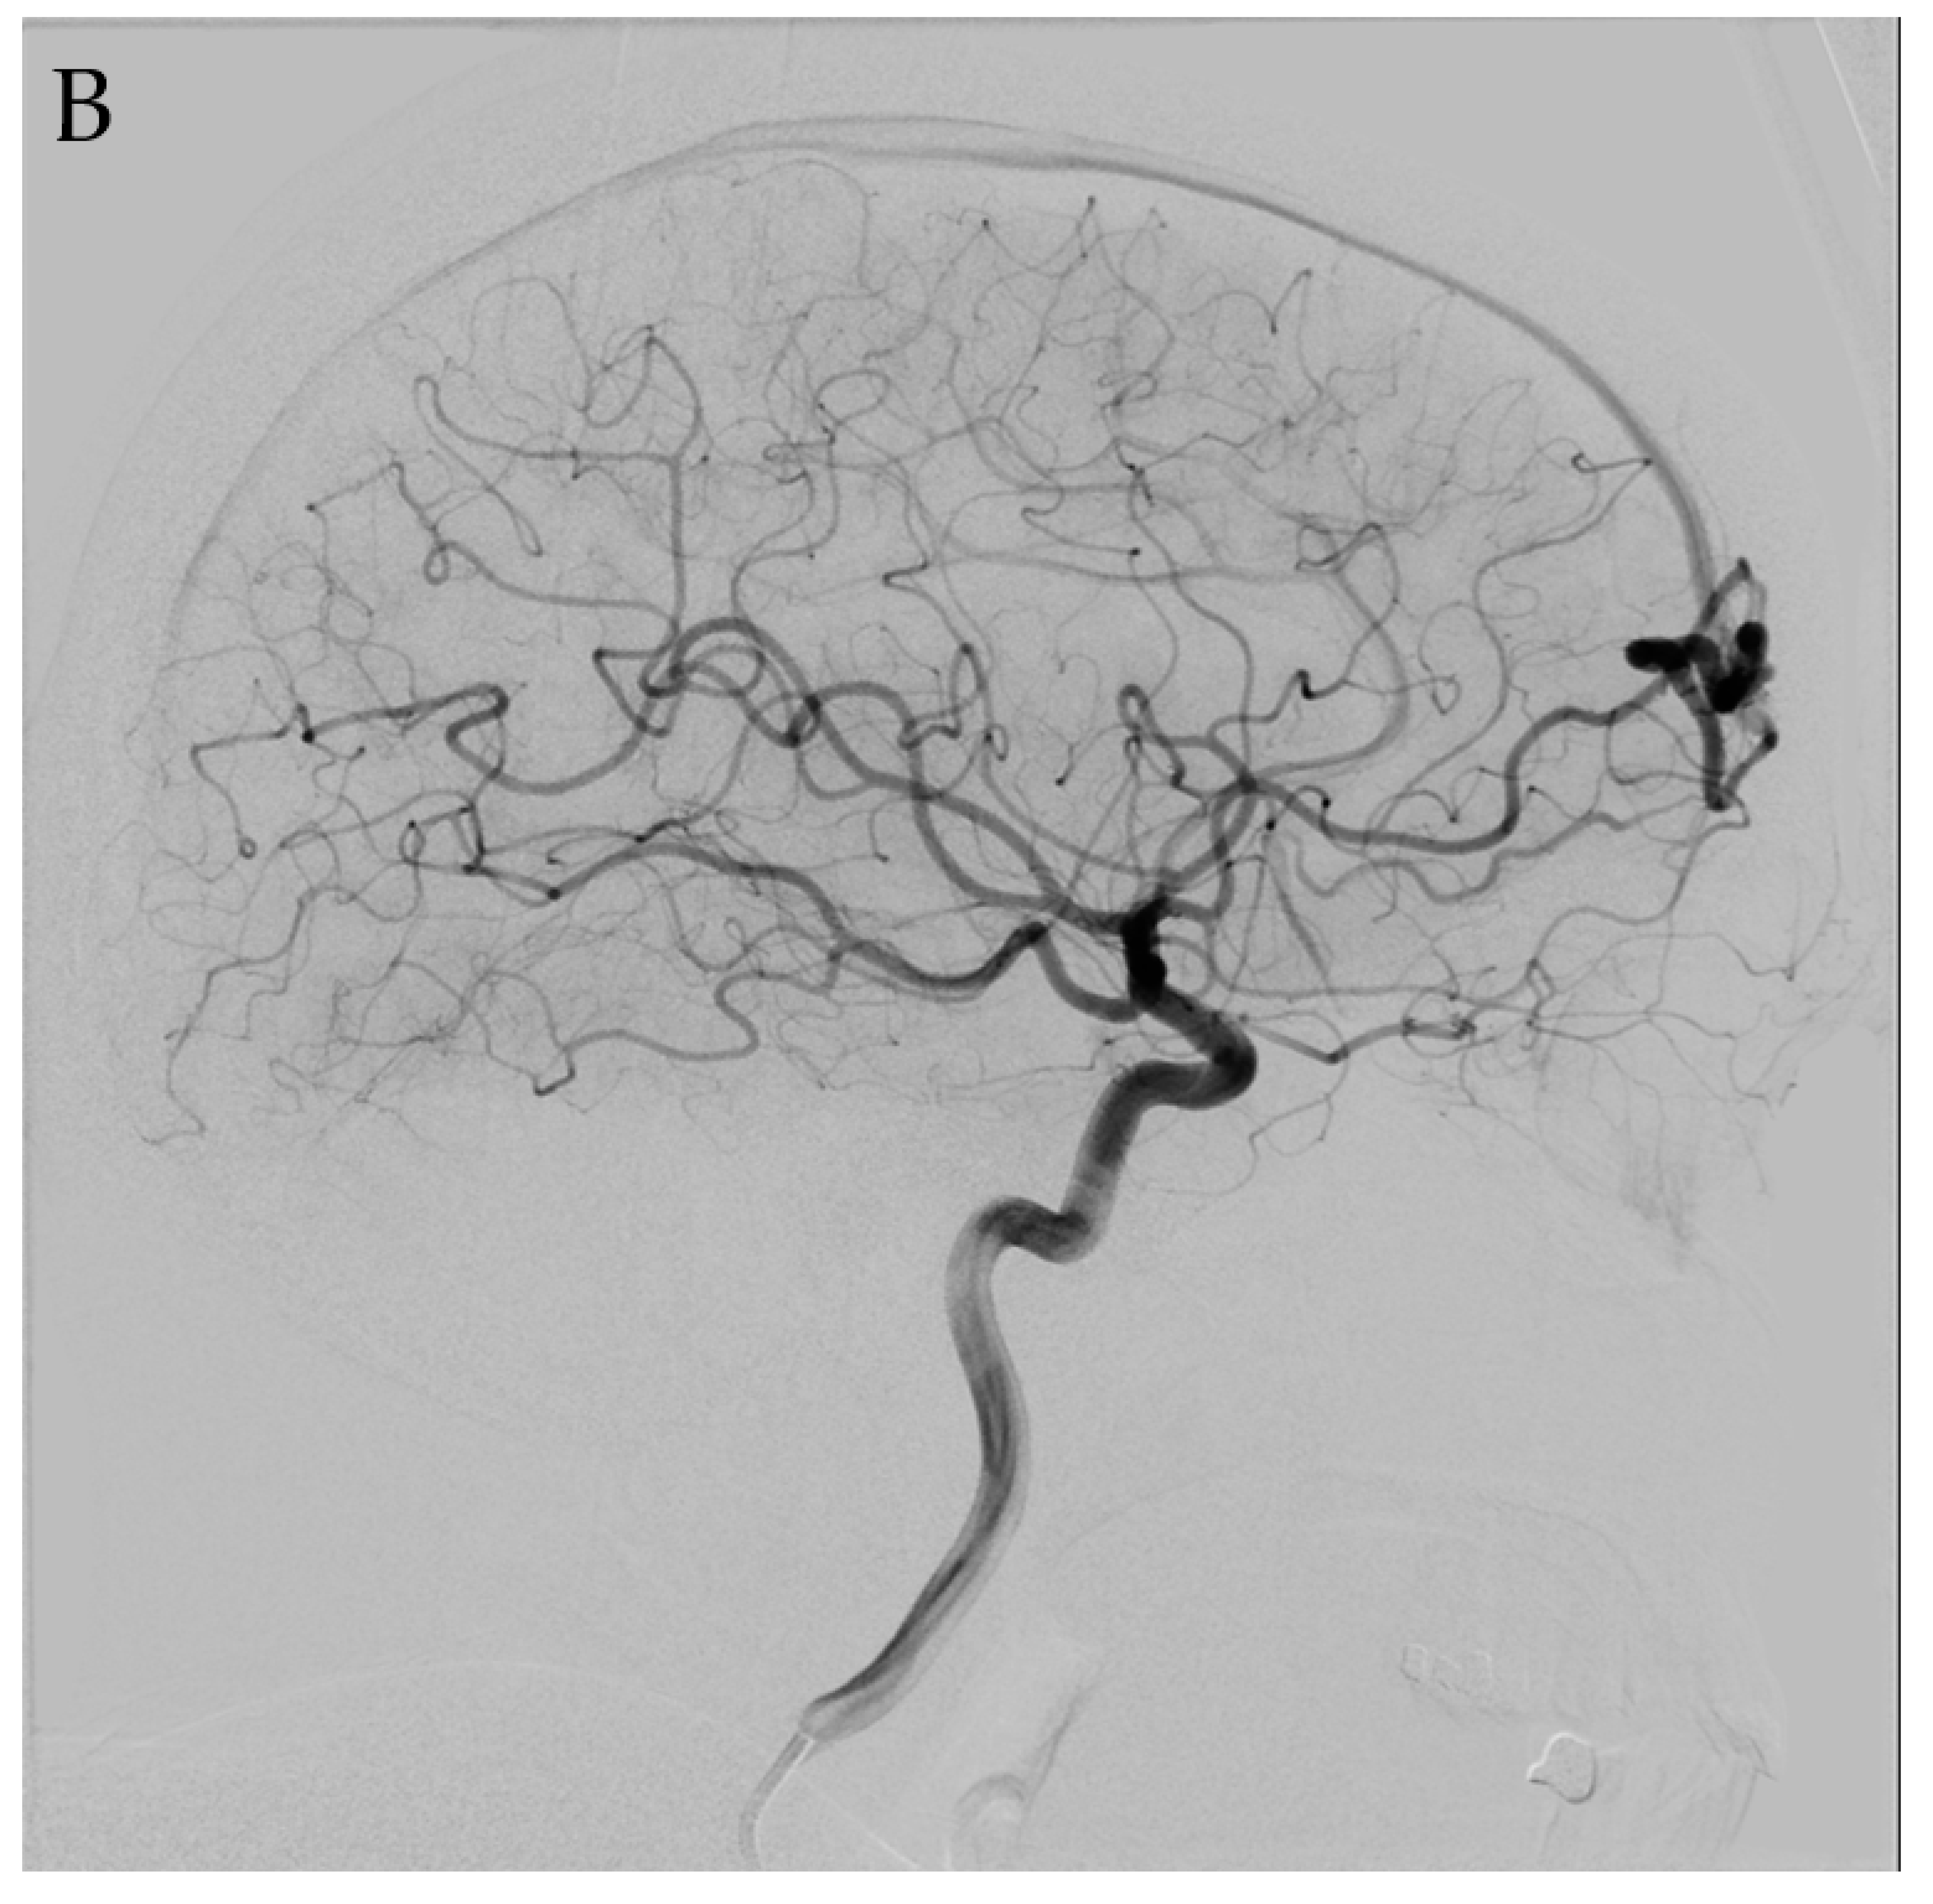

4.1. Microsurgery

4.2. Endovascular Embolization

4.3. Stereotactic Radiosurgery

4.4. Multimodality Therapy